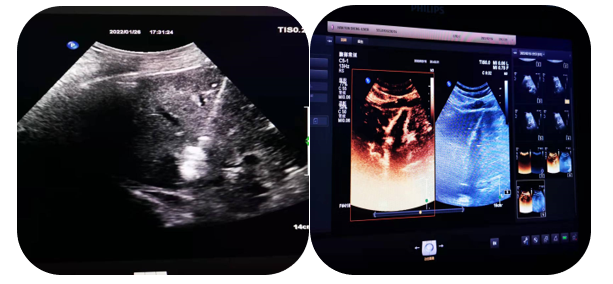

4.超聲介導(dǎo)下肝占位射頻及微波消融術(shù)

通過射頻電極發(fā)出高頻率射頻電流,電能使局部組織發(fā)生正負離子震蕩,并摩擦生熱達100°左右,熱能逐漸傳導(dǎo)至周圍組織,形成一個預(yù)定的球形或類球形的消融區(qū),腫瘤局部因高溫而發(fā)生凝固壞死。以達到和手術(shù)切除同樣的目的和效果。

5.超聲介導(dǎo)下囊腫硬化治療

局部麻醉患者清醒狀態(tài)超聲直視下穿刺針進入囊腫囊腔內(nèi)抽出囊液,注入硬化劑,手術(shù)時間短,損傷輕微,痛苦小,安全性高。